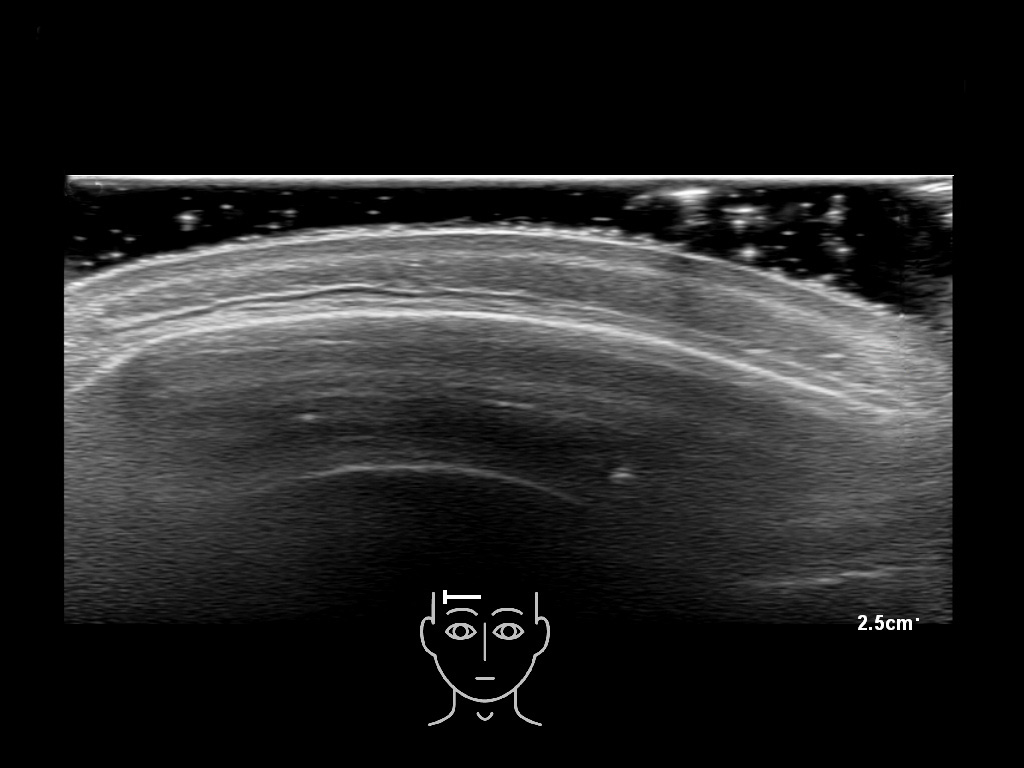

In this section you will learn more about the different layers of the face with the use of ultrasound. When you click on the secondary ultrasound image, you will see the different structures as an overlay. This will help to train yourself to recognize the different layers of the face.

Study the first image to recognize the different layers. If you are sure about the layers, swipe to the second image to view the answer (if applicable).